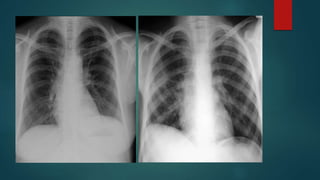

CXR  Lateral decubitus*CXR requires at least 75 ml of fluid  CXR PAV requires at least 150 ml of fluid to be detected  Supine CXR are fallacious to detect pleural effusion  CXR PA view d/ds Subpulmonic effusion Costophrenic and cardiophrenic recesses Blunting of hemidiaphragm Homogenous fluid dense radio-opacity in the lung field and making meniscsus without any bronchovascular markings within Large effusions causes underlying lung collapse and mediastenal shift to opposite side

Exceptionally on CXR Loculated pelural effusion and effsuions in fissures are non dependent  Parapneumonic effusions are difficult to be detected on CXR Grading of effusion on CXR  Mild - Up to causing CoP angle blunting  Moderate - In between  Massive - almost entire hemithorax opaque with collapsed lung